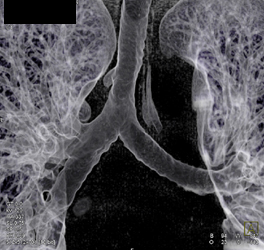

Diagnosis

Pulmonary Arteriovenous Malformation (PAVM)